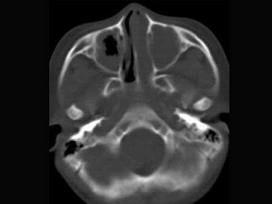

问题 男,7岁,无意发现鼻腔肿物,无明显症状,CT如图所示,最可能诊断为 ( )

选项 A、鼻乳头状瘤 B、鼻炎及副鼻窦粘膜下囊肿 C、鼻炎 D、鼻炎鼻息肉 E、鼻淋巴瘤

答案 D